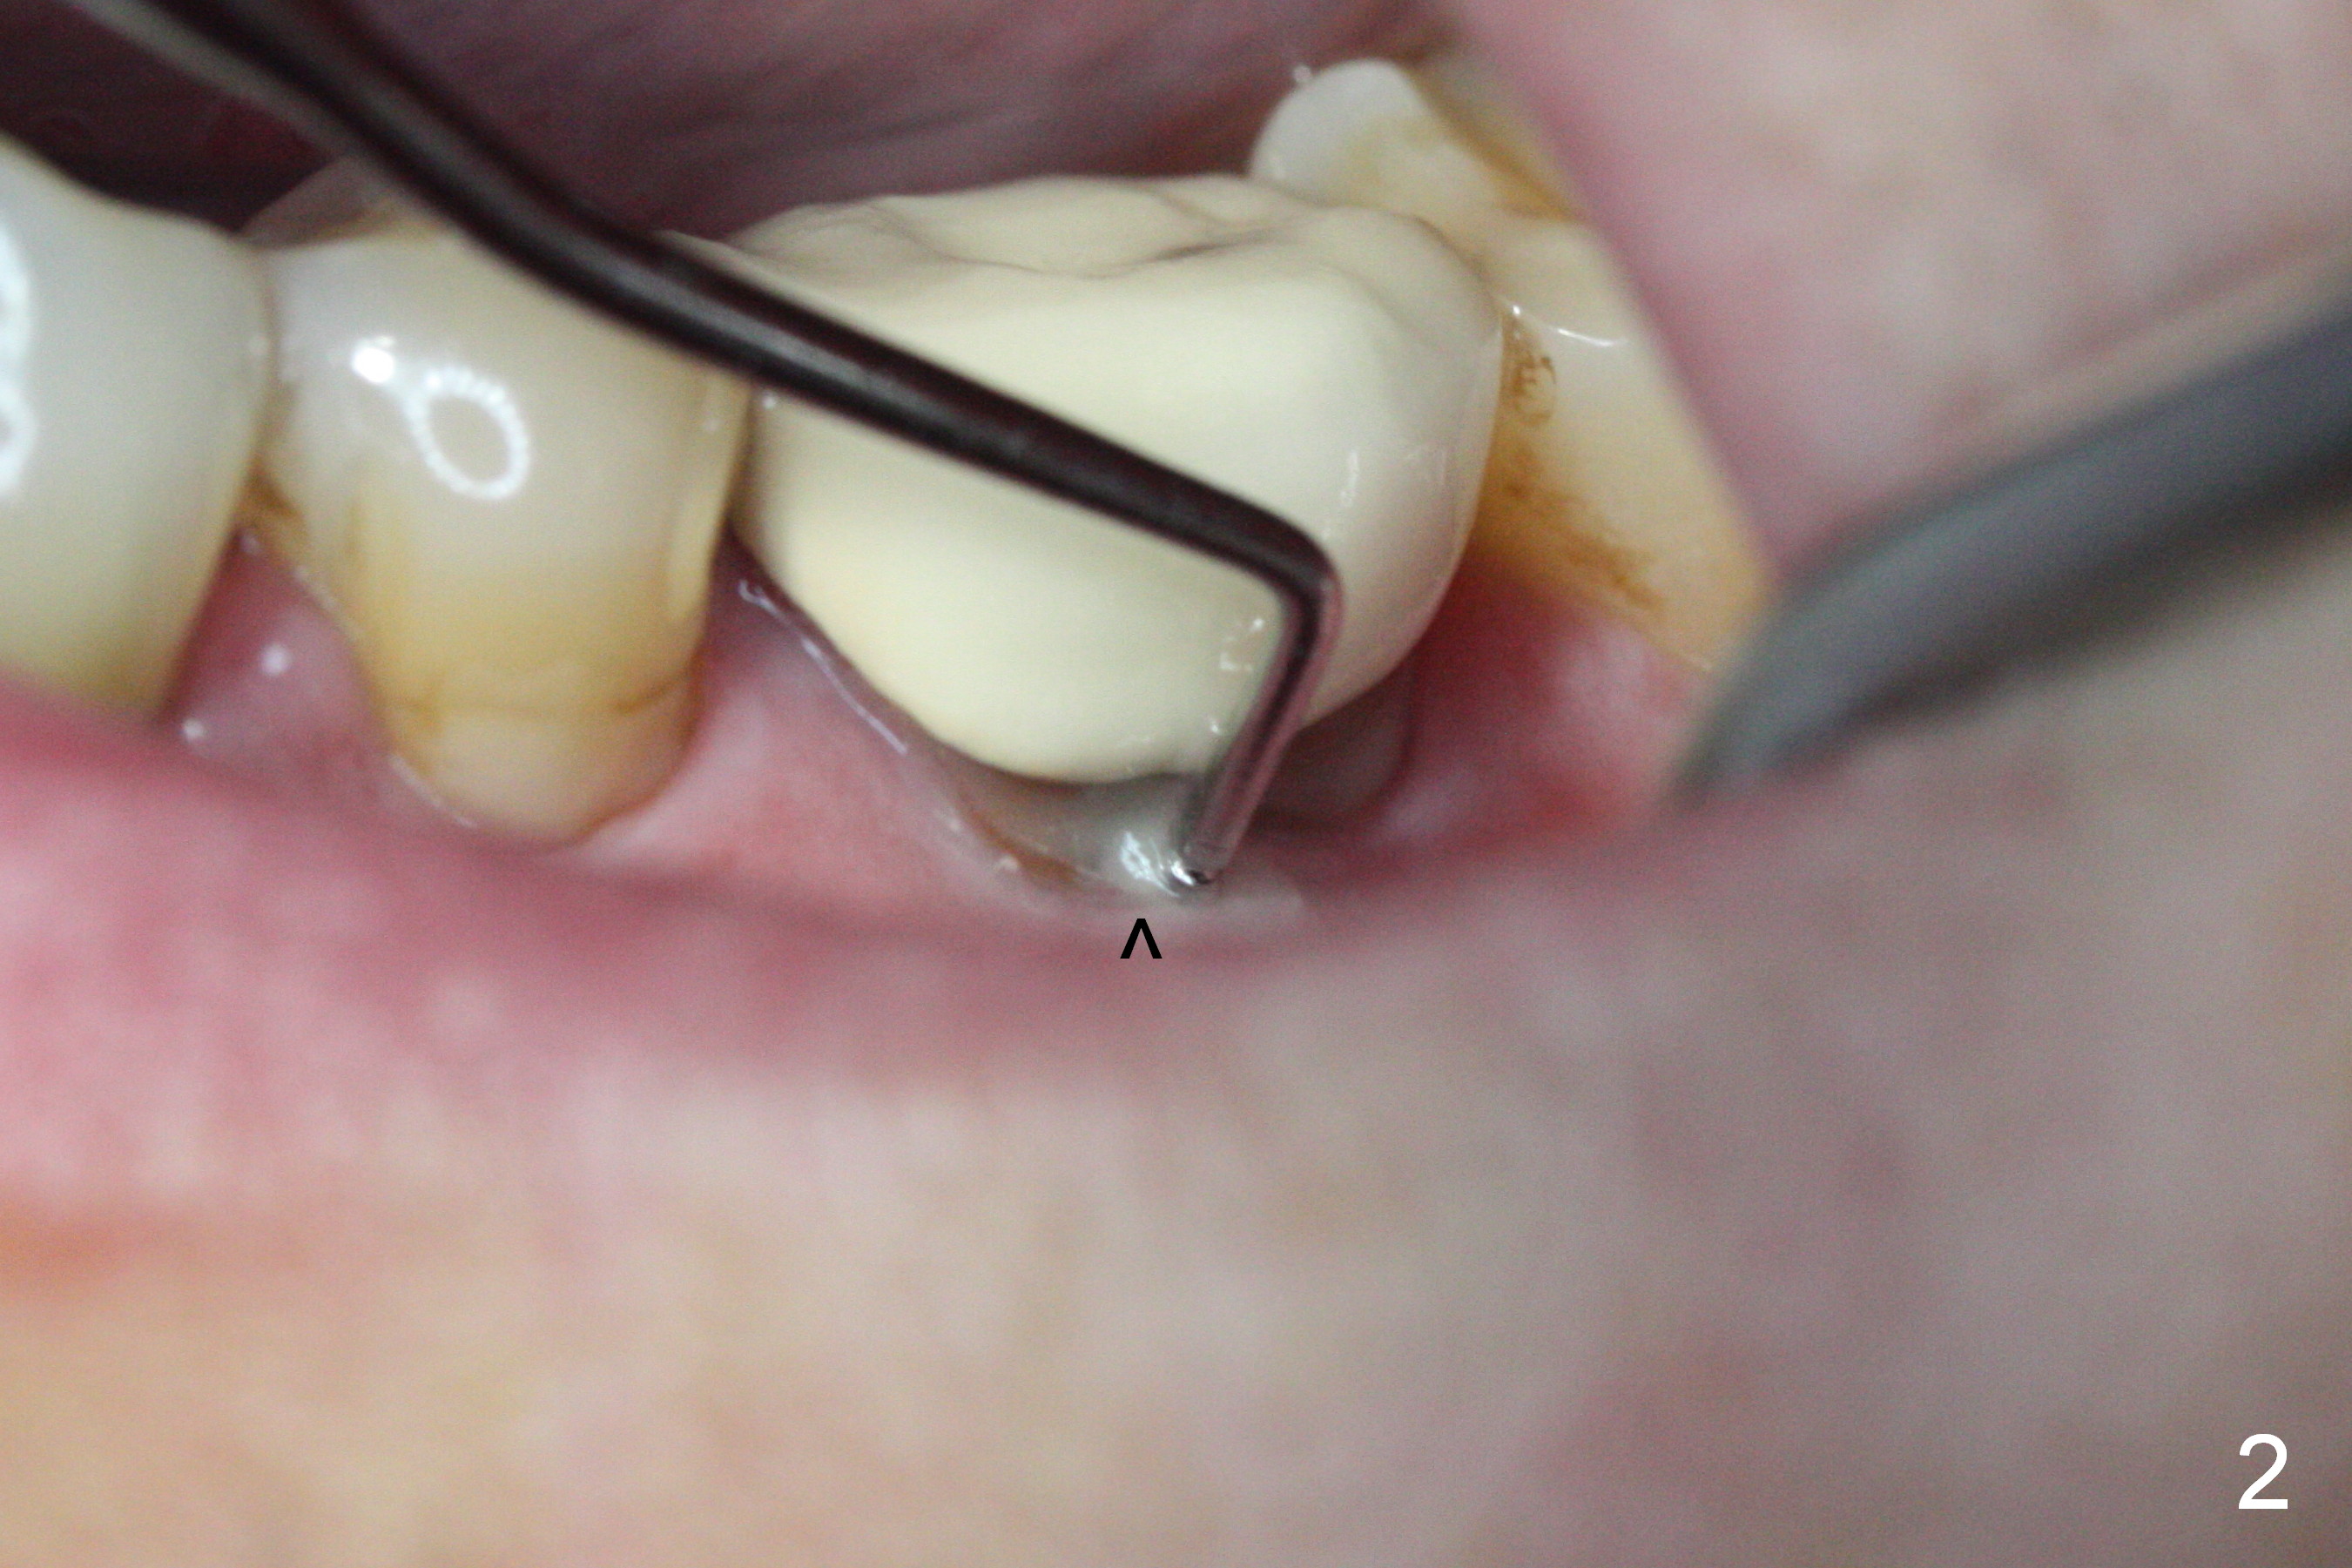

The asymptomatic tooth (#19) has a midbuccal fistula (Fig.1 <). The mesiobuccal pocket is 10 mm with purulent discharge from the sulcus (Fig.2,3). The mesiobuccal wall defect is confirmed when the tooth is extracted. Osteotomy is initiated lingually in the septum following septal crestoplasty (flattening) (Fig.4: using 1.6 mm drill for 9 mm). Since the lingual portion of the osteotomy is higher, it is difficult to use drill with stopper. For the narrow septum osteotomy, multiple drills are used sequentially (Fig.5 after 4.3 mm drill). A 4.5x11 mm dummy implant is placed (Fig.6) apparently too deep. When a 5x11 mm IBS implant is being placed, the depth is tightly controlled (Fig.7). The implant is apical to the lingual crest, whereas there is ~ 2 mm implant exposure buccally. That is, there is a large gap mesiobuccally (Fig.8), which is filled with .5-1.5 mm allograft (Fig.9 *). A 6.5x5.7(3) mm abutment (A) is placed and trimmed for an immediate provisional (Fig.10 P). The lacerated buccal gingiva is sutured as well as application of Perio Glue.